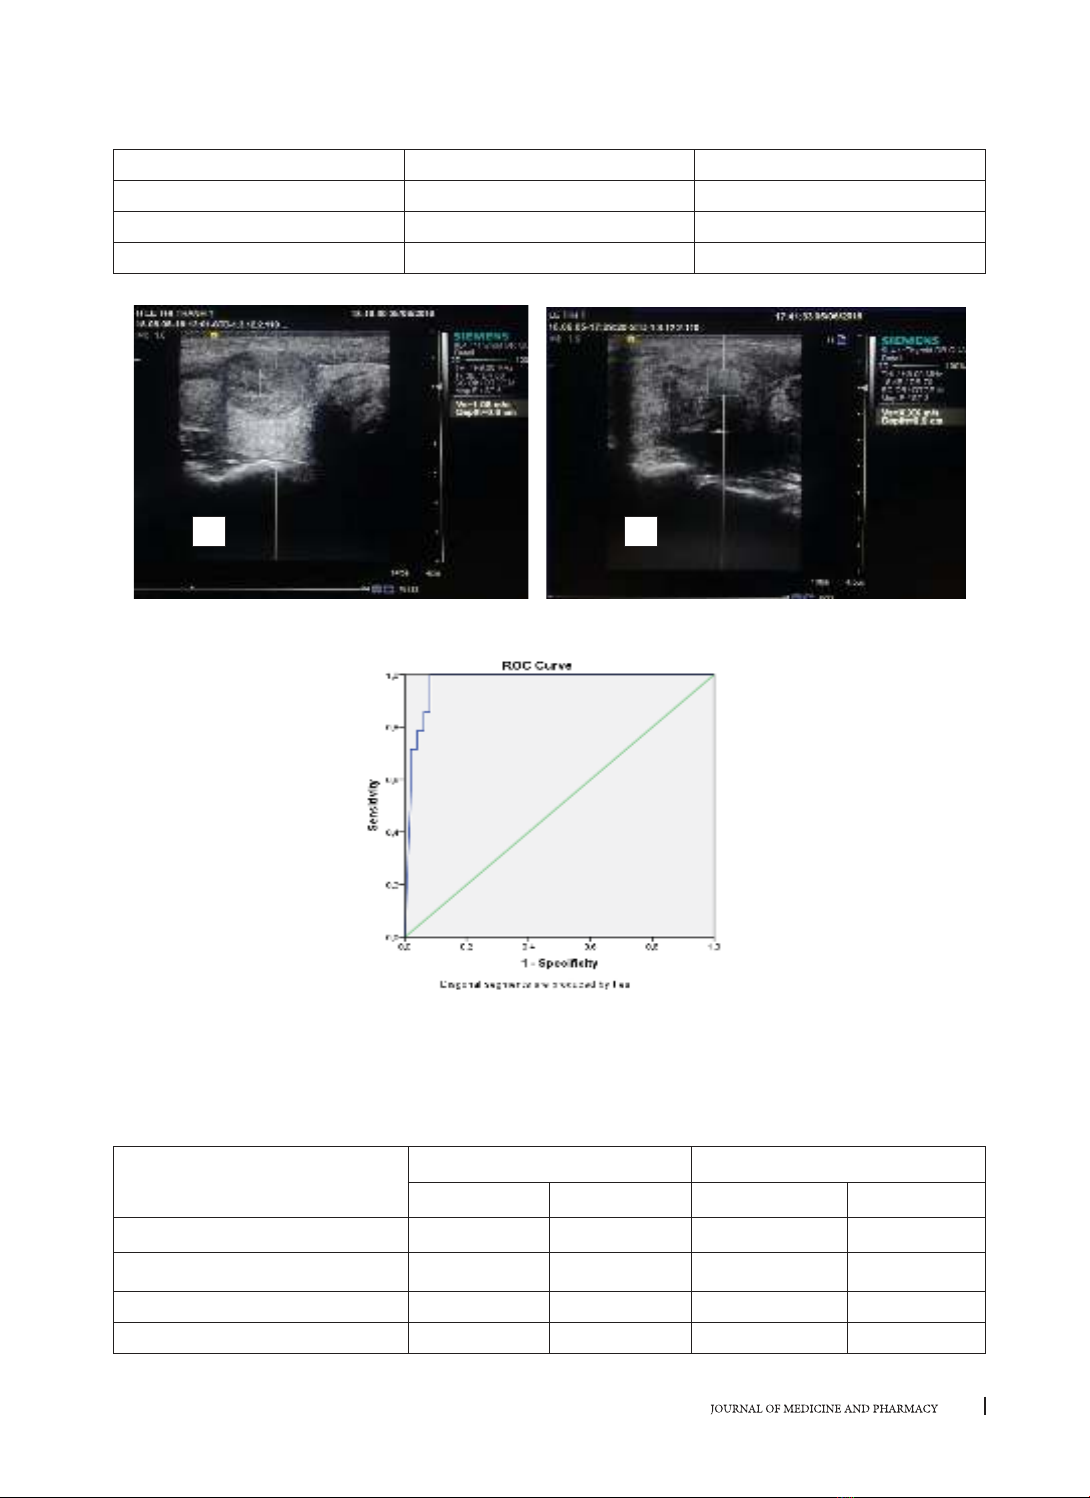

Hình 1. Giá trị vận tốc sóng biến dạng tổn thương lành tính SWV=1,08 m/s (A)

và tổn thương ác tính SWV= X.XX m/s(B)

Biểu đồ 3.1. Đường cong ROC giá trị vận tốc trung tâm sóng biến dạng trong chẩn đoán phân biệt

tổn thương lành tính - ác tính

Nhận xét: Điểm cắt trong chẩn đoán phân biệt tổn thương lành - ác là 2,40 m/s với Se = 100%, Sp = 91,8%,

Acc = 93,7%, PPV = 77,8%, NPV = 100%.